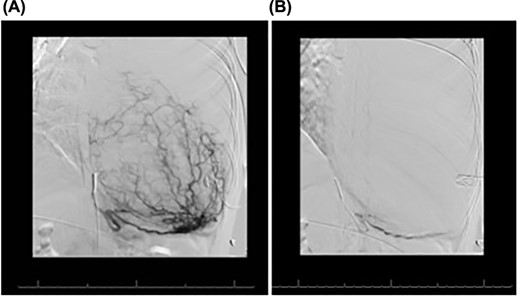

A 33-year-old woman presented to the emergency department following a motor vehicle accident. Imaging showed a large heterogenous intermediate density mass filling and expanding the left hemithorax, causing a complete collapse of the left lung and substantial right deviation of heart and mediastinum (Fig. 1). The patient complained of mild exertional dyspnea that had worsen over the past 6 months. Physical exam was unremarkable aside from decreased breath sounds on left side. Percutaneous core needle biopsy revealed spindle cells along with immunostatins consistent with SFT. Upon later questioning, the patient noted progressive anorexia with a 15 lb weight loss over the last 4 months and occasional dyspnea.

Frontal chest radiograph shows complete opacification of left hemithorax with significant mass effect.